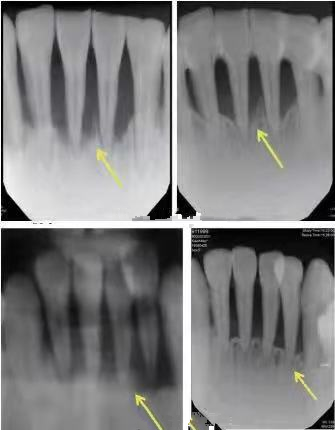

使用喷砂洁牙后的口内效果对比图

瑞士Ems牙周全能治疗仪Air-Flow Master Piezon带来洁牙新体验,全面清除牙菌斑,实现理想的口腔洁治效果,清除烟渍色素还原牙齿本色,缓解牙龈牙周炎症。